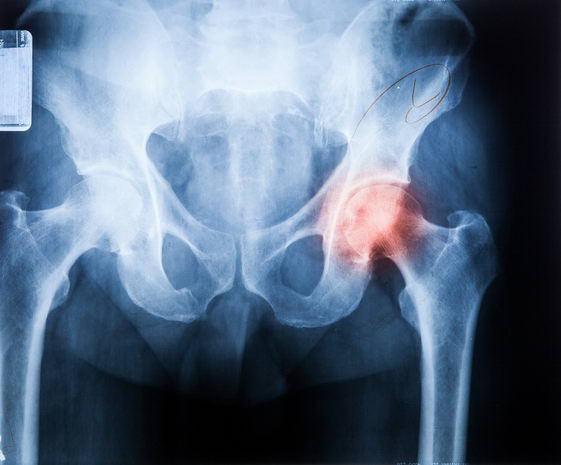

一个超过26,000位英国中年女性 (年龄在35-69岁) 的研究发现,相比规律吃肉的人,吃素者髋部骨折风险多了33%。

英国University of Leeds的研究,调查偶尔吃肉者、只吃鱼但不吃肉者、素食者、以及规律吃肉的髋部骨折的风险。

26,318位女性中,在大约20年的观察,822位有髋部骨折,代表了样本人口中刚好超过3%。即使将潜在干扰因素调整之后,髋部骨折险增加的唯一群组是素食者。干扰因素包括:人种、社会人口、婚姻状况、更年期、生育孩子数目、心血管疾病、癌症、糖尿病、运动、抽烟和营养补充品的使用等。

原因:营养摄取不足?低BMI值?

研究主导作者James Webster说:“素食者在骨骼和肌肉健康相关的营养素摄取较少。这些种类的营养,如蛋白质、钙、B12和其他微量营养素,在肉和其他动物制品中较丰富。摄取不足会导致骨质密度和肌肉量的下降,较易有髋部骨折的风险。”

此外,BMI值亦可能是原因。

研究团队发现素食者比荤食者,平均BMI稍微较低。之前的研究显示低BMI和髋部折高风险相关。低BMI表示体重过低,骨骼和肌肉量可能不良,有较高风险的髋部骨折。

研究的共同作者Janet Cade教授说:“髋部骨折是全球性的健康议题,经济上花费高,会失去独立性,减低生活质量,增加其他健康问题的风险。以蔬菜为基本饮食与骨骼健康不良有关,但连结到髋部骨折风险的证据一向欠缺。这个研究是了解长期素食潜在风险,以及可采取哪些措施来减轻这些风险重要的一步。”